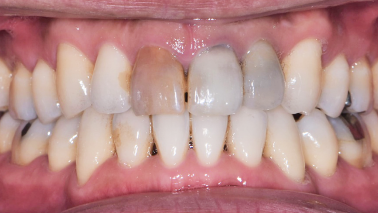

この患者様は長い事歯科医院には通っておらず、下の歯は前歯以外は全て崩壊していることが分かります。

前から見ても歯が欠けてしまい、歯茎も赤く腫れてしまっているのが分かります。

様々なことを鑑み、患者様とも何度も話し合いを行い、下の奥歯には必要最低限のインプラントを、他の歯も外科処置を施しなるべく歯を抜かない方法を取りました。

最終的に抜歯した本数は下の歯5本。上の歯に関しては全て残すことが出来ました。